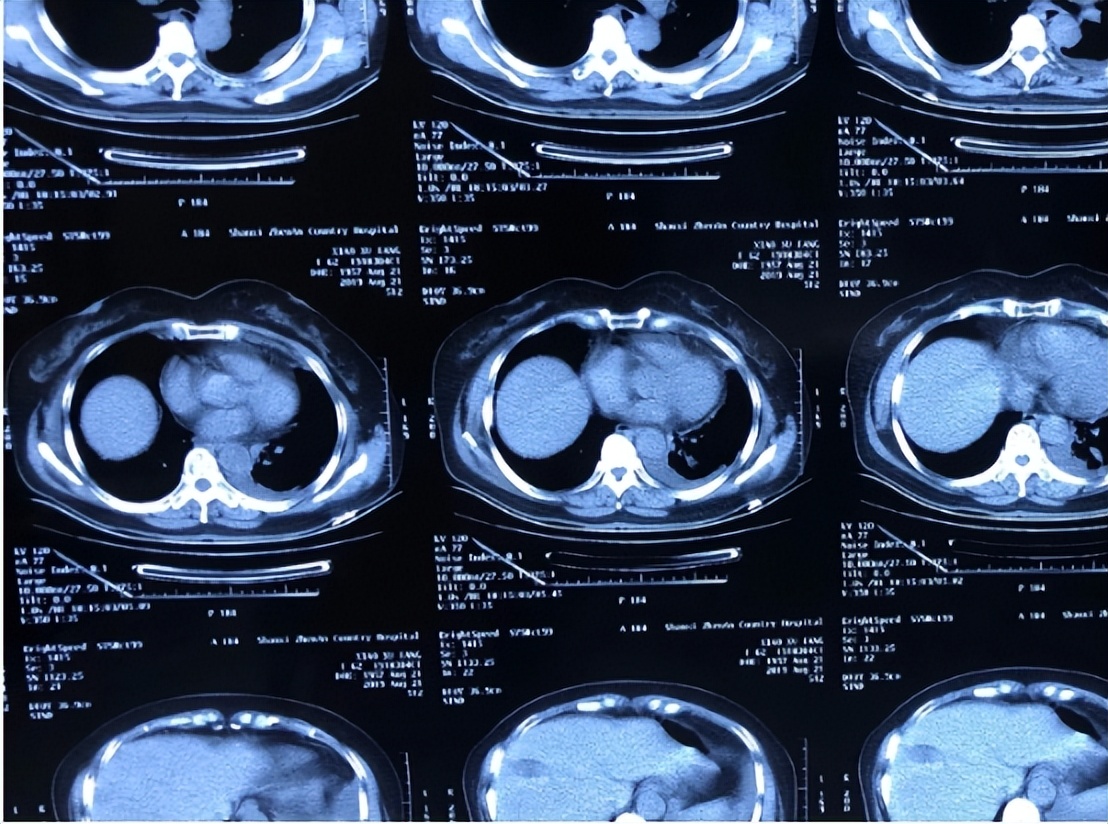

胸腔积液是临床上呼吸系统常见的疾病,病因比较复杂,已知有超过50种肺部、胸膜及其他系统疾病可引起胸腔积液,其诊断通常比较困难。胸腔镜下胸膜活检是诊断不明原因胸腔积液。

胸膜疾病的首选技术,在进行诊断性胸穿和闭合性胸膜活检后,仍有25%的病因未被诊断。

胸腔积液病因复杂。

目前的胸膜活检术的活检组织标本的质量没有统一评价的标准,我们应该选择一种安全的活检技术,能够获得大的活检样本,而不会对组织样本造成任何形态学改变,从而降低额外的取样工作,提高诊断率和工作效率。

冷冻技术在胸腔镜检查中的应用最初是在1989年描述的,理论上我们可以想象,使用胸膜冷冻活检技术同支气管镜下肺的冷冻活检一样,可以获得更大更深的组织,减少标本被挤压变形,从而提高诊断率,另一方面,也增加出血等并发症风险。

然而目前相关文献对胸膜冷冻活检术的诊断率和安全性的研究结果不一致,这项技术也未纳入临床实践指南之中。